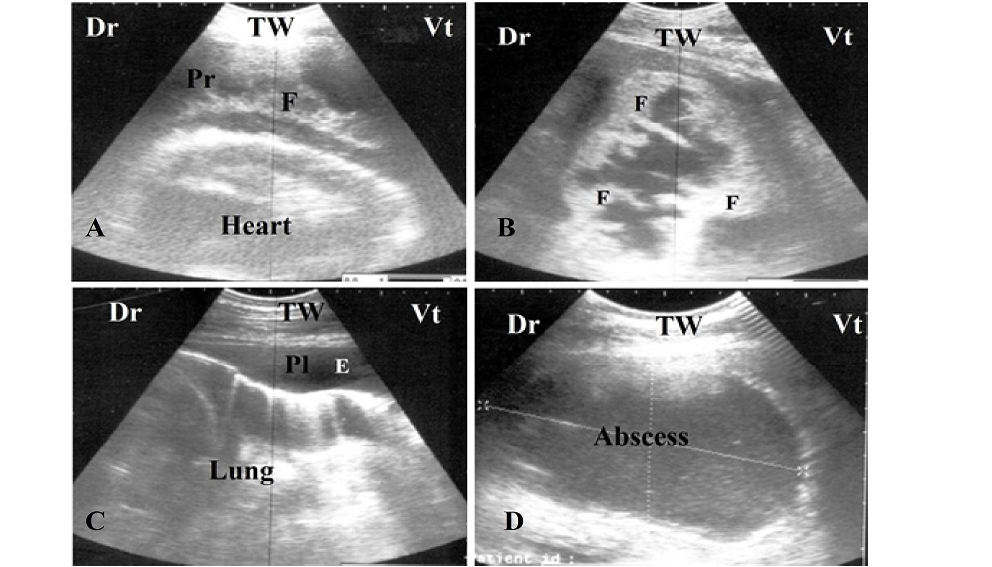

A and B. Ultrasonogram of a buffalo with pericarditis, notice the presence of echogenic fibrin (F) interspersed in pericardial sac (Pr);

C. Ultrasonogram of pleurisy, notice the anechoic pleural effusion in pleural sac (Pl) and absence of reverberation artifact of lung;

D. Circumscribed abscess with echogenic capsule and hypoechoic pus content locates in mediastina between lung, heart and thoracic wall (TW). Dr: dorsal, Vt: ventral